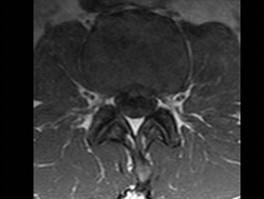

问题 男,45岁,背部隐痛半年余,请结合影像学检查,选出最可能的诊断 ( )

选项 A、椎间盘突出 B、神经根鞘囊肿 C、硬膜外纤维化 D、椎管内肿瘤 E、椎间盘炎

答案 A